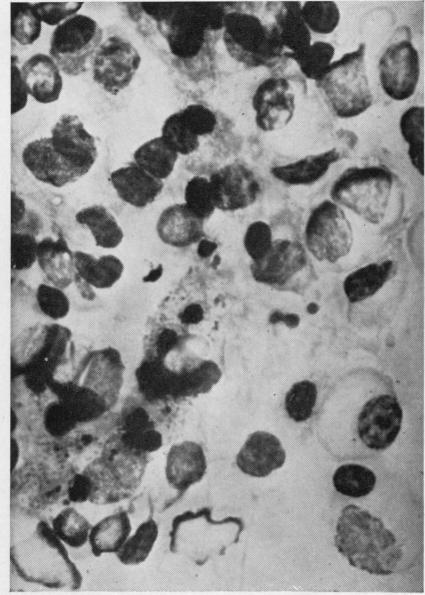

The clinical course and pathological features of four cases of Waldenström's macroglobulinaemia are described. One was associated with a localized carcinoma of the bronchus and one with a chromophobe adenoma of the pituitary. Trypsin digest preparations of the retina were examined in two cases, one with severe retinopathy and the other with no clinical evidence of ocular disease, and the findings are briefly described. The aetiology of the anaemia is discussed. Haemolysis due to circulating autoantibodies was not demonstrated in any of the cases. Erythrophagocytosis was a prominent feature in case 4, of moderate degree in cases 1 and 2, and inconspicuous in case 3. It was not proportionate to the serum macroglobulin levels. The cytological and histological features in all four cases are distinctive, and their value in differential diagnosis is stressed.

本文描述了4例华氏巨球蛋白血症的临床病程及病理特征。其中1例与支气管局部癌有关,1例与垂体嫌色性腺瘤有关。对2例患者的视网膜进行了胰蛋白酶消化制剂检查,1例有严重视网膜病变,另1例无眼部疾病的临床证据,并简要描述了检查结果。文中讨论了贫血的病因。所有病例均未证实存在由循环自身抗体导致的溶血现象。红细胞吞噬现象在病例4中较为突出,在病例1和2中程度中等,在病例3中不明显。其与血清巨球蛋白水平不成比例。所有4例的细胞学和组织学特征均有独特之处,并强调了它们在鉴别诊断中的价值。